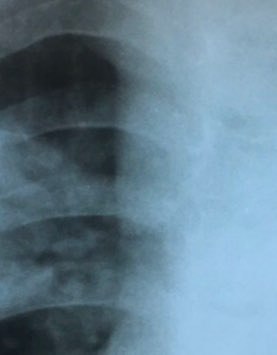

Я думаю пневмония

Справа поддиафрагмальная грыжа

Образование только я вижу ?

Я не настаиваю, вижу так)

Пневмония с реакцией плевры

Верхний контур по ребру идёт согласен, а Левее смотреть

Думаю ,это тимус

Предварительно правосторонняя сегментарная S2  плевропневмония, 5 дней антибиотиков, делаем контроль при отсутствии динамики, или ухудшения ФБС и с нашей стороны подозрение на органическое поражение Б-2.

Или субкапсулярное скопление жидкости?

Операция была по поводу холецистактомия